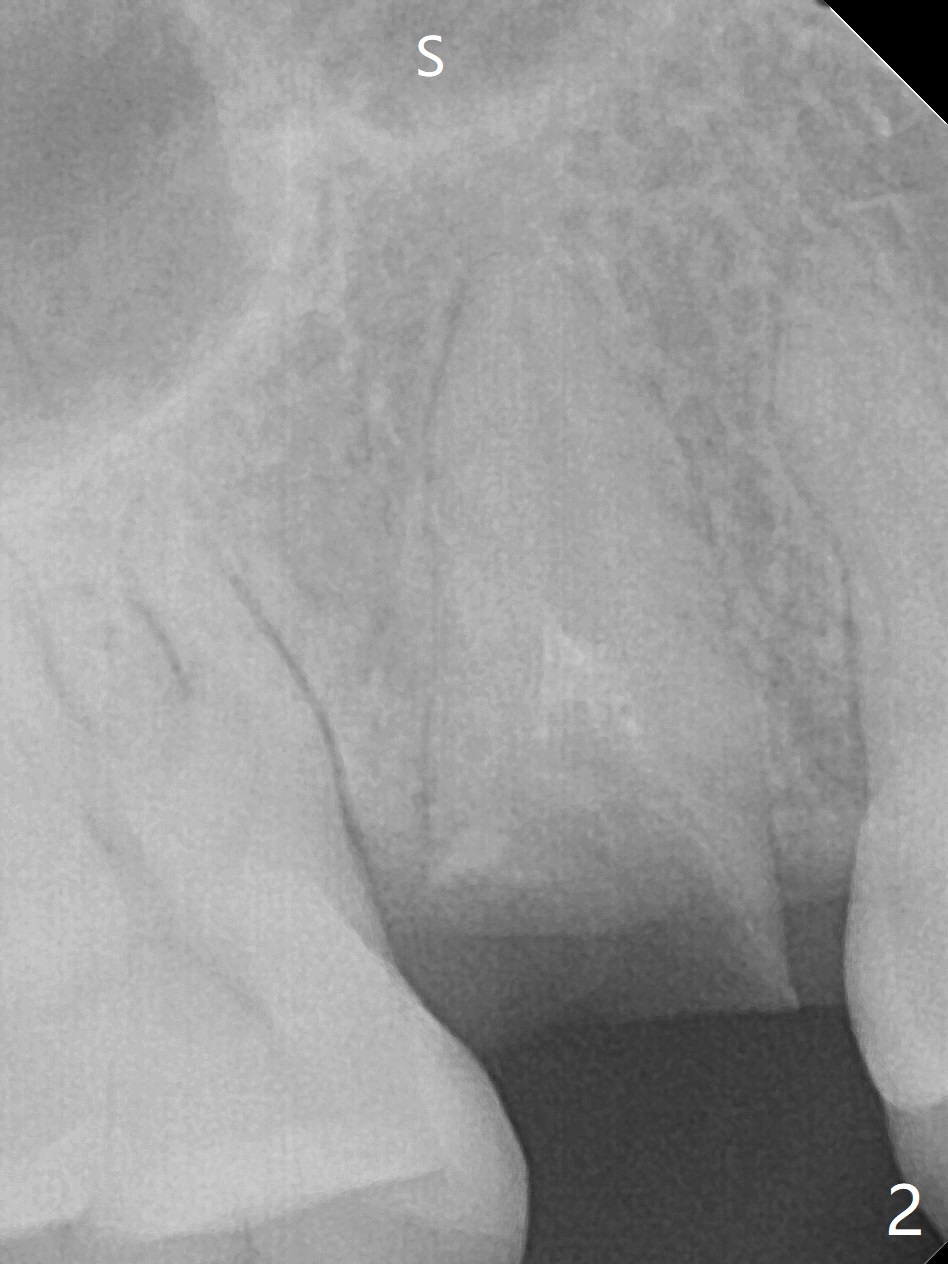

Barely Penetrate Sinus Floor

A 29-year-old woman requests implant for the residual root of the tooth #4 after initial RCT in home country (Fig.1,2 (S: sinus)). It appears that a 15 or 16 mm long implant should be placed to engage into the apical native bone and sinus floor (*) for stability (Fig.3,4). Further stability is obtained by contact with the mesial (M), distal (D) wall or both.